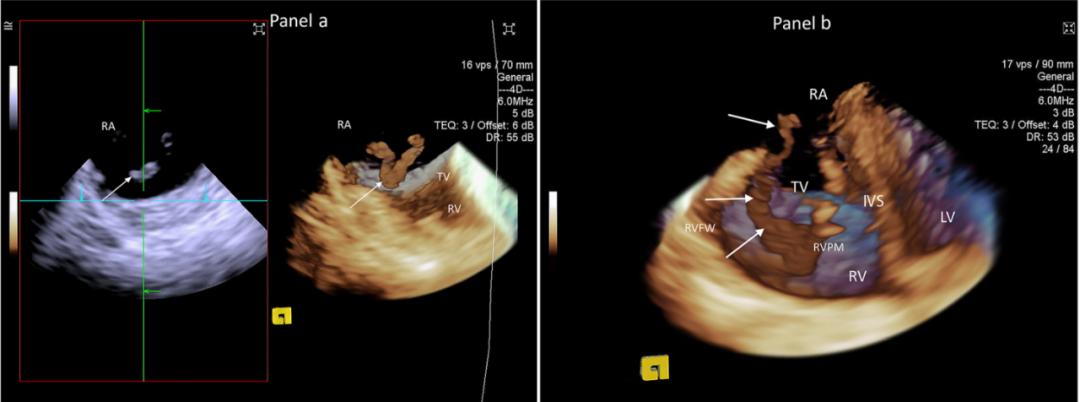

图2. 心腔内三维超声技术心脏图像[7]

[7] Three-dimensional intracardiac echocardiography and pulmonary embolism. Cardiovasc Ultrasound. 2020 Aug 20;18(1):36. doi: 10.1186/s12947-020-00220-3. PMID: 32819376; PMCID: PMC7441699. Yastrebov K, Brunel L, Paterson HS, Williams ZA, Bannon PG.